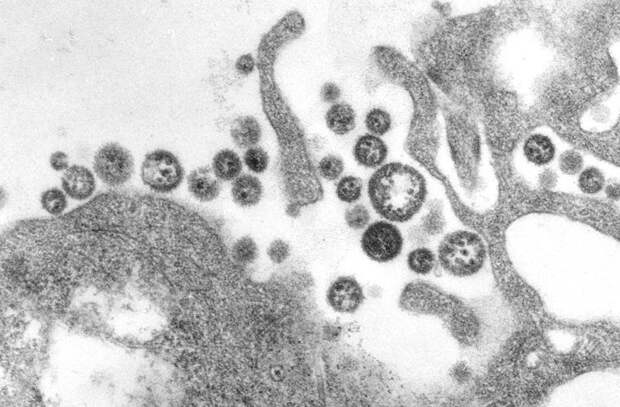

Вирус желтой лихорадки

Будучи практикантом в одной из пенсильванских больниц и решив опровергнуть версии о заразности болезни, Фирф был крайне изобретателен в доказательных методах. Закапывая рвотные массы, полученные от больных, себе в глаза, поливая ими разрезы, сделанные на теле и даже выпивая их в большом количестве, Фирф так и не заразился. Однако он глубоко заблуждался в своей теории. Все дело в том, что желтая лихорадка передается при попадании в кровоток, обычно при укусах комаров. К сожалению, эта информация впервые появилась спустя 60 лет после смерти Стаббинса Фирфа — в работах кубинского врача Карлоса Финлея, а экспериментально была подтверждена лишь в 1900 году.